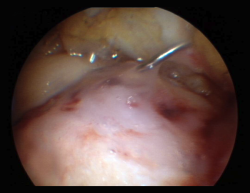

This section includes GelrinC® (Regentis Biomaterials, Akiva, Israel), based on a mixture of polyethylene glycol diacrylate (PEG-DA) and denaturalized fibrinogen, that reacts upon being exposed to ultraviolet light, with transformation into a semisolid gel. A comparative study with microfracture alone is also ongoing at this time in the United States, with a view to obtaining approval of the product. Another option among the hydrogels is CartiFill® (Sewon Cellontech, South Korea), based on atherocollagen, and which has been in use for some years in several countries (Figure 3).

Figure 3. Arthroscopic filling of a femoral trochlear ulcer with CartiFill®.